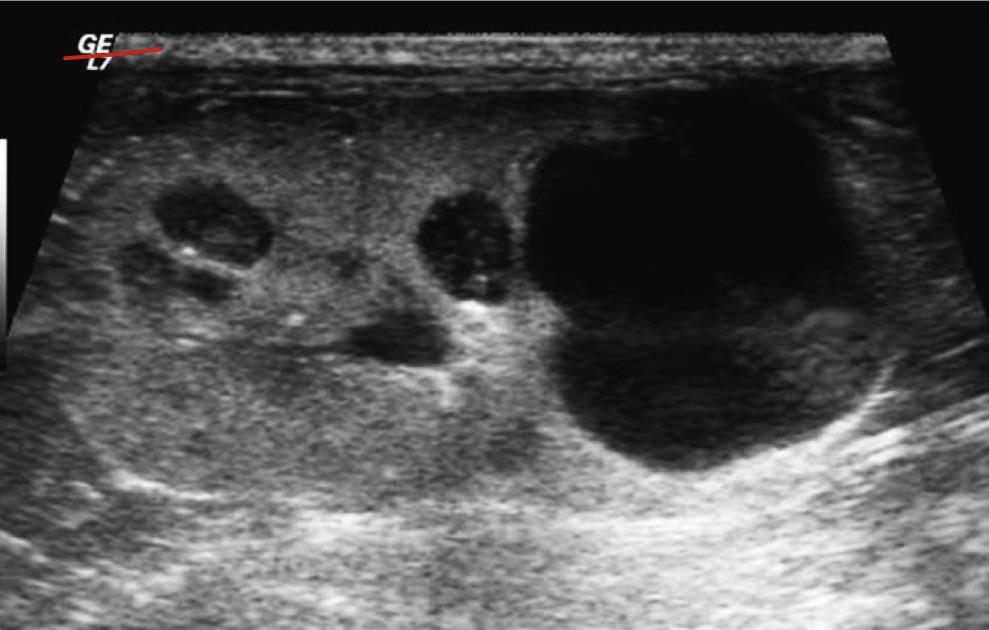

Liver

What organ is most prominent in this ultrasound?

Hepatomegaly

What is occurring in this patient?